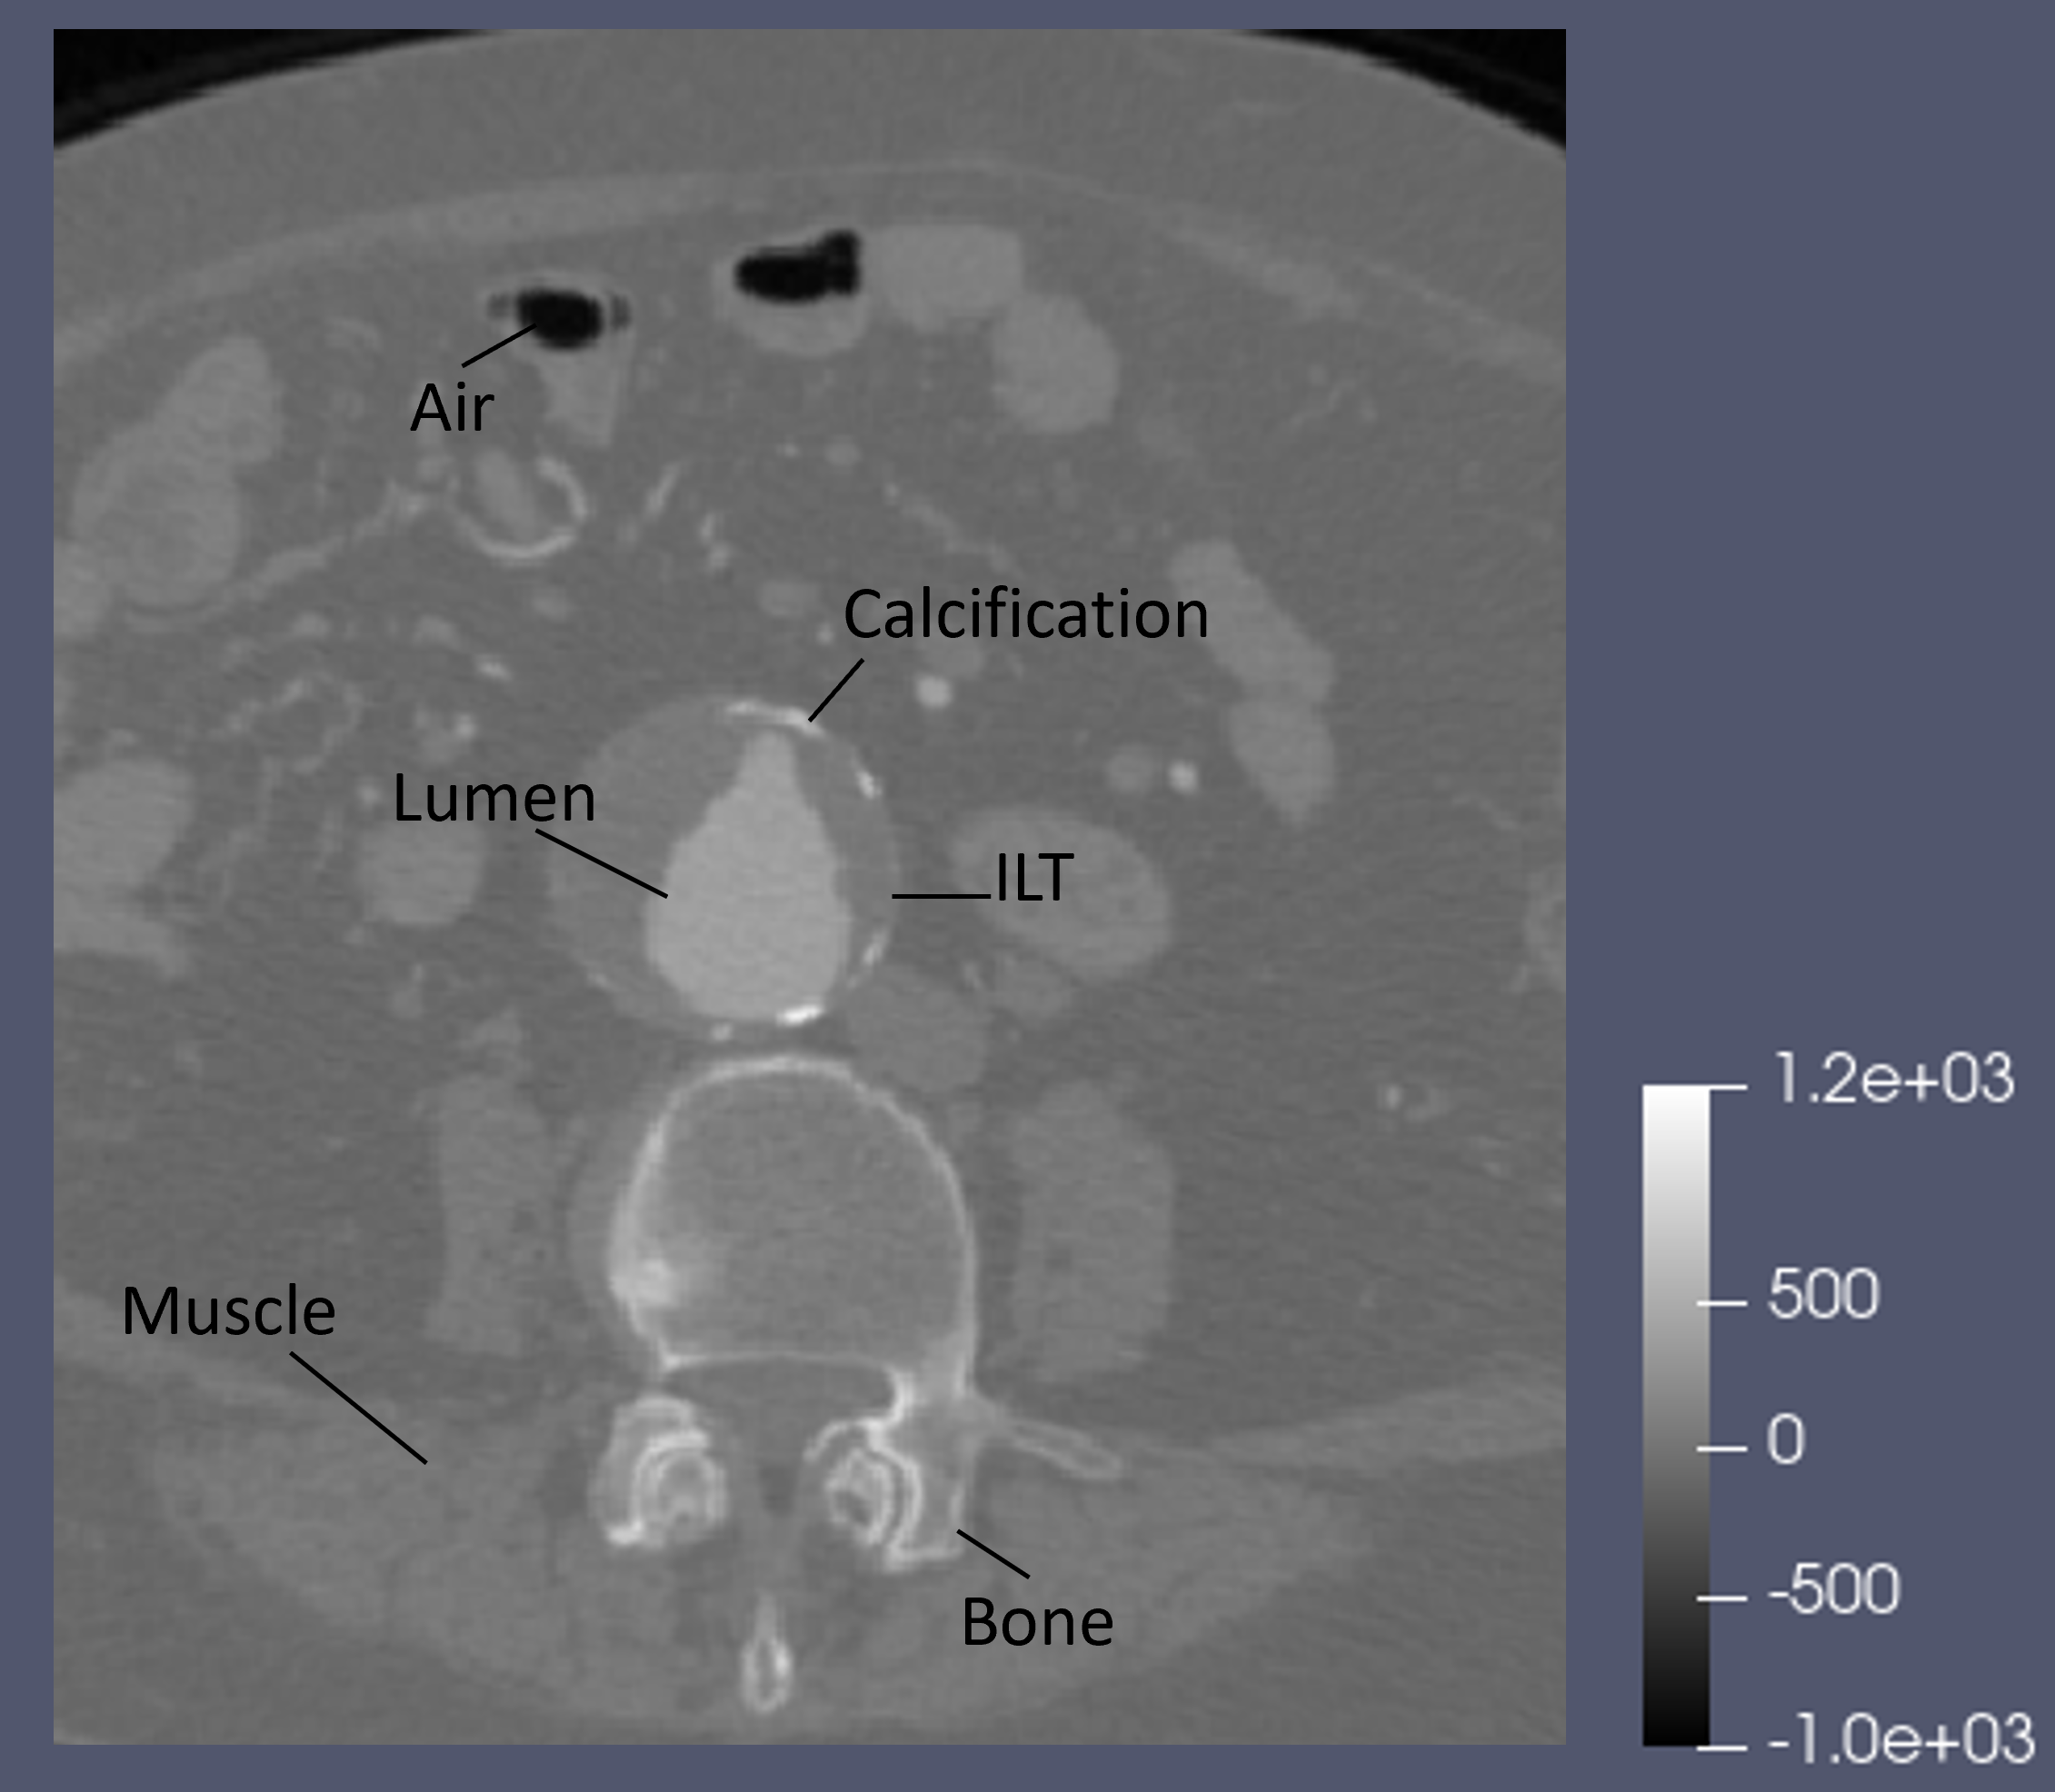

Refer to caption

(b) Coronal slice of a CTA scan. Different shades of grey differentiate between different organs and tissues. This allows both the clinicians to see the entire anatomy of the patient and the algorithm to execute the segmentation process.

Figure 1: Schematic representation of an Abdominal Aortic Aneurysm and a CTA scan.

3.1 CTA scans

The most used and effective method for anatomy visualization is Computed Tomography Angiography. CTA is used to get a visualization of the human body and is realized with emission of X-rays through a tomograph. A CTA scan consists of a 3-dimensional image of a region of interest in the form of a volume composed by voxels with different shades of grey. Each shade is associated to a different tissue, making it possible to distinguish not only between fat, bones and muscle but also artery, intraluminal thrombus (ILT) and calcification - see also Figure 1(b).

Two main features characterize the aneurysm: intraluminal thrombus (ILT), thrombus for short, and wall calcification. The former is the stratification of several blood particles in the inner layers, the latter is the accumulation of calcium in the aortic wall responsible of its stiffening. Both negatively affect the aorta changing its physiological behavior by modifying the lumen’s structure, the region where the blood flows, with bumps and irregularities.